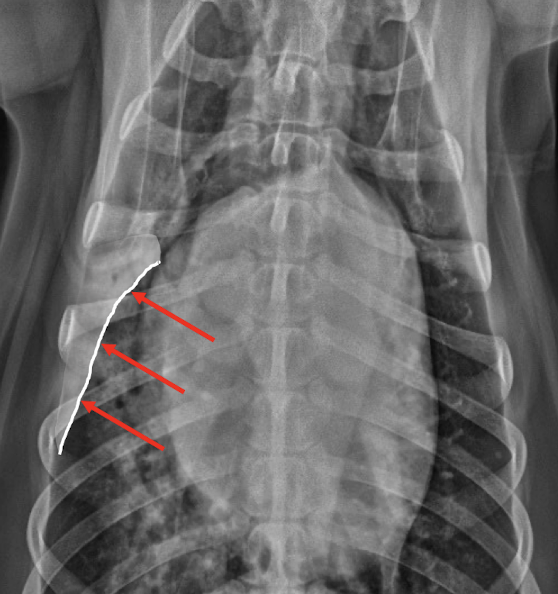

What is highlighted?

Pleural fissure lines

What is the appearance of pleural effusion on radiographs?

Widened pleural fissure lines Lungs retracted and rounded